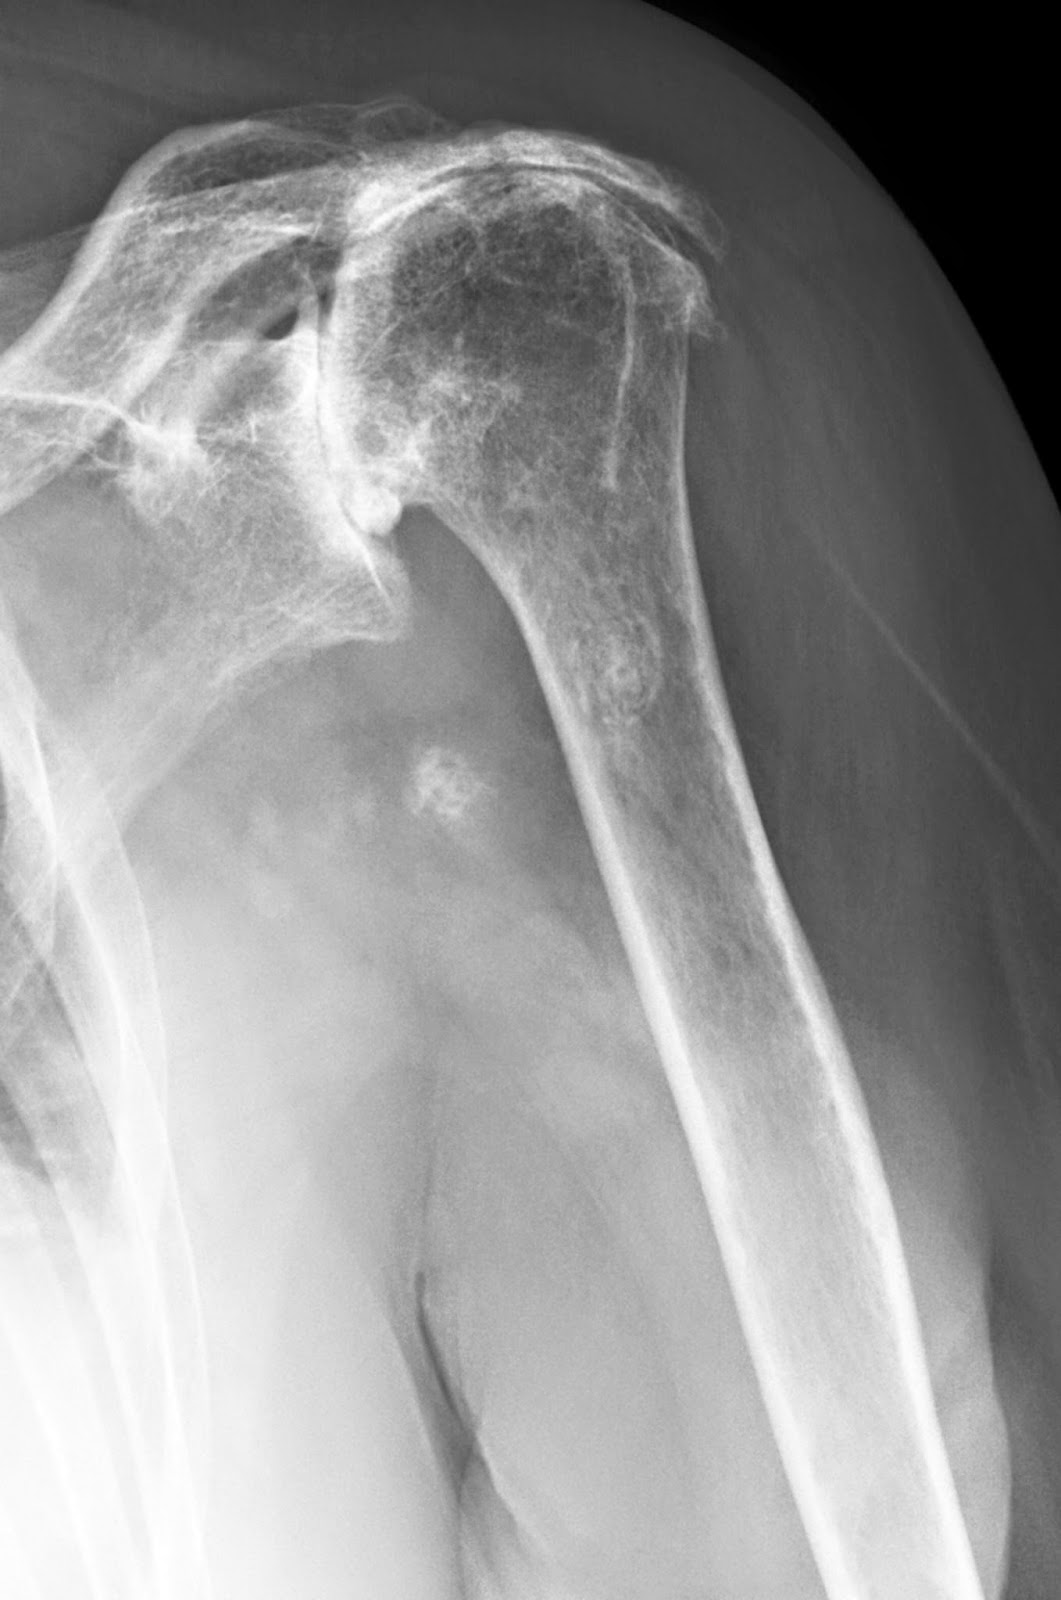

Partial or Total Shoulder Replacement Dr Skedros Orthopaedics Arthritis In Shoulder Rotator Cuff Pain from a problem with the rotator cuff is. rotator cuff tear arthropathy is a type of shoulder arthritis that can develop after a massive and prolonged rotator cuff tear. the rotator cuff is a group of muscles and tendons that keep the upper arm bone held in the shoulder blade socket. rotator cuff tear arthropathy (or. Arthritis In Shoulder Rotator Cuff.